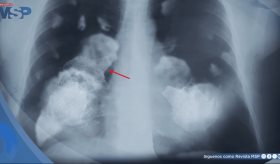

Dado que los síntomas de esta afección son similares al de las enfermedades cardíacas, pulmonares, problemas gastrointestinales y la osteoartritis, dependiendo el riesgo de cada caso, se pueden realizar exámenes para descartarlas, como un electrocardiograma o radiografía de tórax.